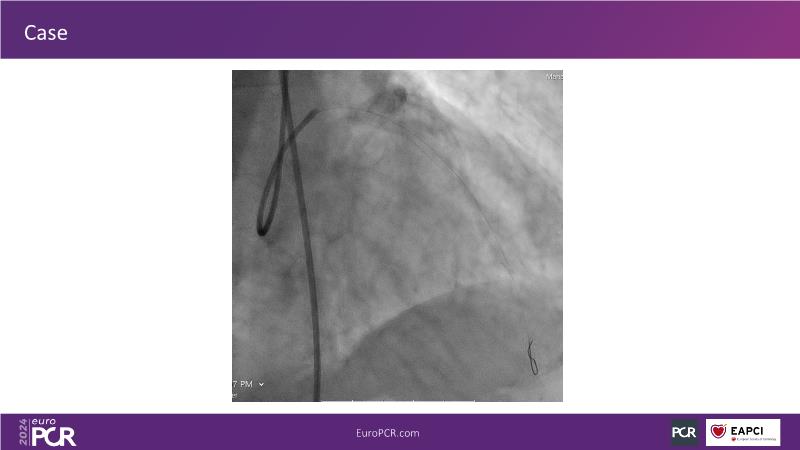

Tune into this 2024 session for insights into the latest ESC guidelines, strategies to prevent and treat no reflow, and an examination of trials like TASTE, TAPAS, and TOTAL on coronary thrombus management. Explore also the outcomes of the CHEETAH study, pondering a potential paradigm shift, and delve into a case study on thrombus removal in a patient with high thrombus burden.